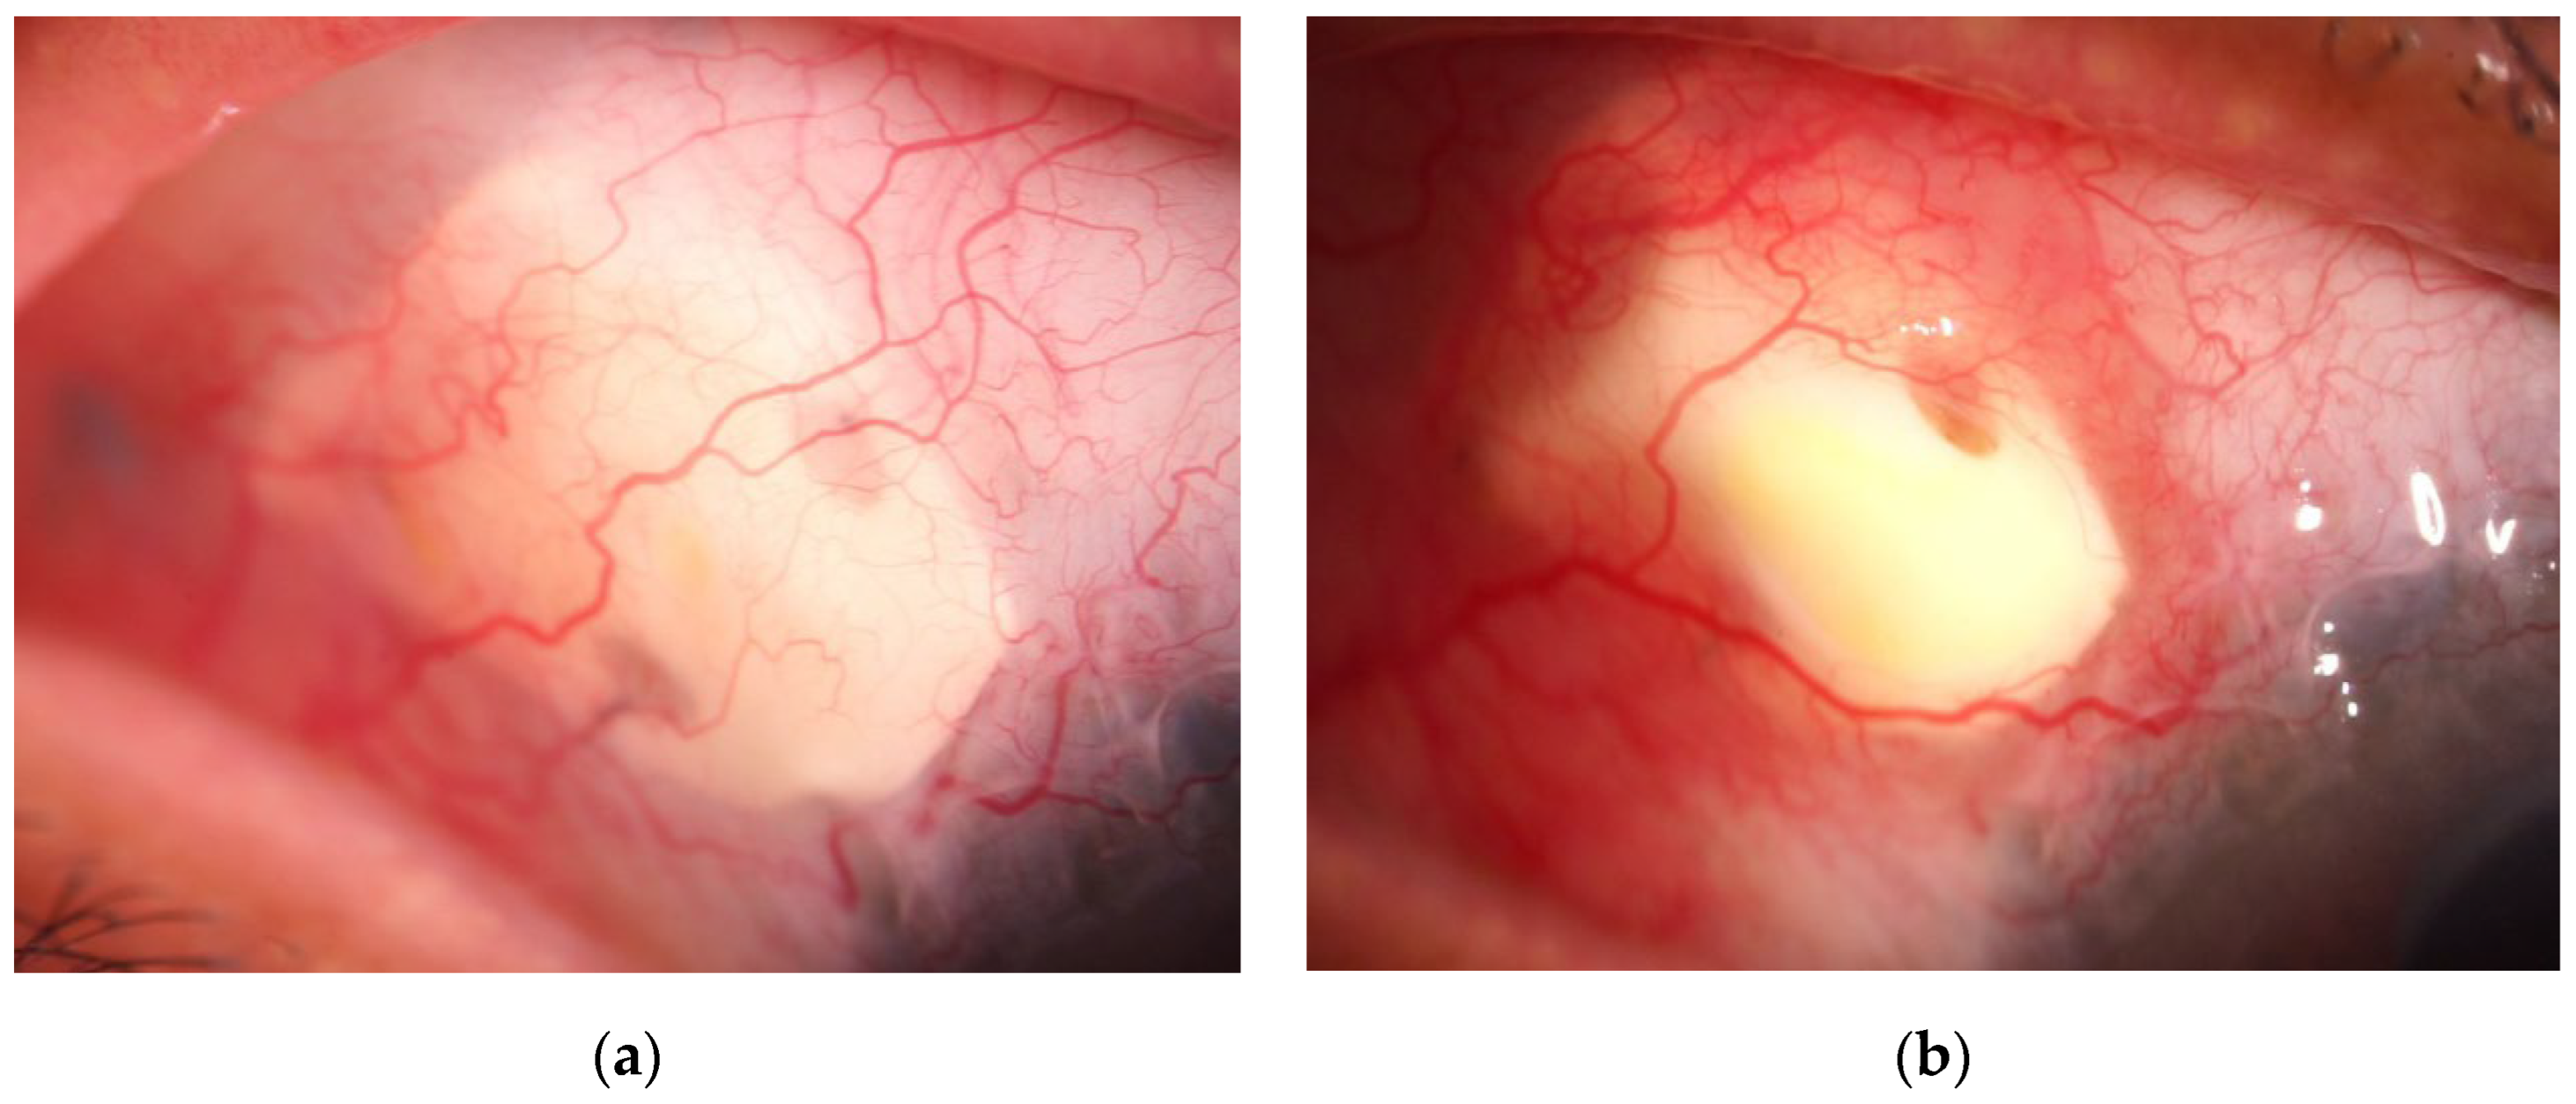

Two distinct patterns of EverPatch extrusion were identified. In one of the three extruded cases, the edge of the EPP mechanically disrupted the overlying conjunctiva leading to exposure of the EPP (Figure 6 a,b). The clinical course in this case was comparable to that observed in conventional scleral patch graft-related extrusion.

A different pattern of extrusion was observed in 2 of 19 eyes treated with EPP, characterized by conjunctival bleaching followed by progressive melting of the overlying conjunctiva. The initial ischemic change developed in the anterior central portion of the EPP. (Figure 7 a, b). This pattern of extrusion was not observed in any of the 12 scleral patch graft cases with extrusion, representing a statistically significant difference between groups (P=0.024 Fischer exact test).

Figure 7. a, b. Slit-lamp findings in a case of central-type extrusion. Representative slit-lamp photographs illustrating the clinical course of an EPP extrusion case. (7a) Appearance at 6.7 months postoperatively. Prior to extrusion, demonstrating decreased vascularity over the anterior central portion of the patch. (7b) Appearance at 8.9 months postoperatively, showing progression to conjunctival melting and subsequent patch exposure. This type of extrusion began as a small dimple in the central area of EPP and progressed rapidly, leading to conjunctival melting and subsequent exposure of the patch.